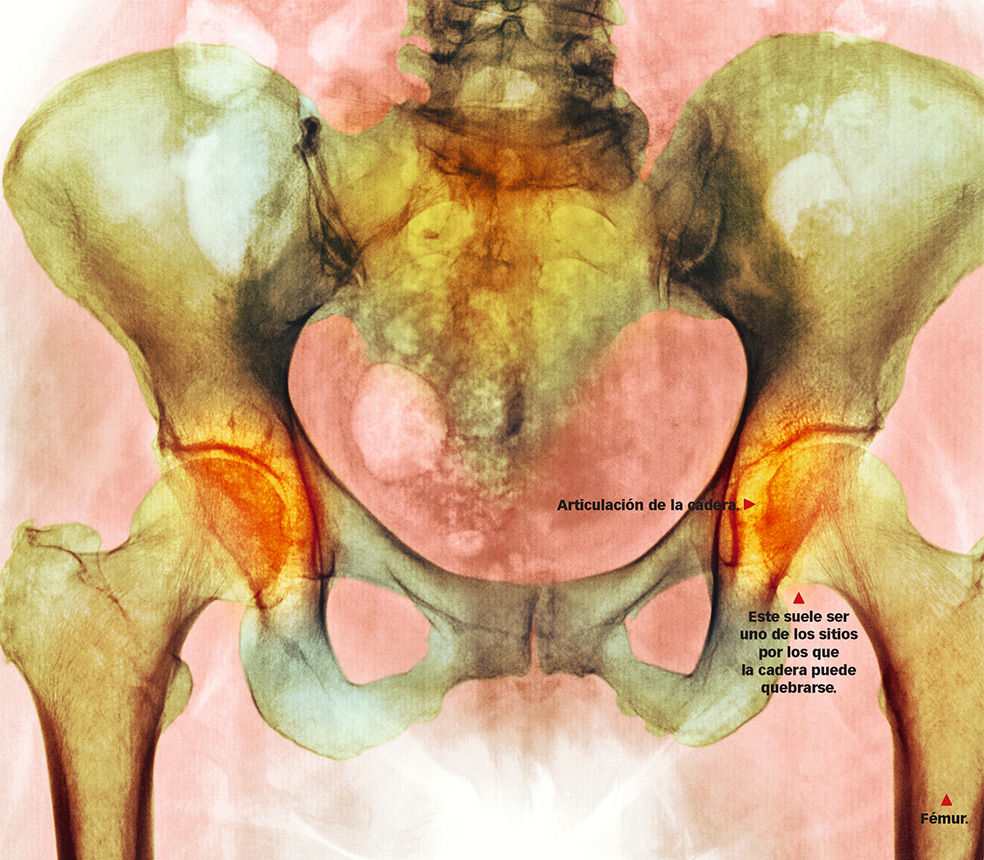

Si el coste de la enfermedad es alto (más de 126 millones de euros en costes directos y de 420 millones en costes indirectos), el sufrimiento que generan las fracturas es enorme. De las tres fracturas típicas de la osteoporosis –cadera, columna y muñeca–, la más grave es la de cadera. Se calcula que, en los próximos 10 años, la sufrirán más de 260.000 mujeres y más de 84.000 varones; la mitad, a partir de los 77 años. Las consecuencias son dramáticas: al cabo de un año habrán fallecido el 30 por ciento de quienes la sufran; a los dos años, el 40 por ciento.

¿Qué es? La disminución de minerales en los huesos y la reducción de la zona cortical por un defecto en la absorción del calcio, que los vuelve quebradizos y susceptibles de fracturas y microfracturas.

¿Por qué ocurre? Todo depende de la cantidad de masa ósea acumulada hasta los 30 años, edad del pico de masa ósea, y de la rapidez con que perdamos hueso después de esa edad. Cuanto más masa ósea tengamos en nuestro ‘banco’ personal, menos riesgo de fracturas tendremos.